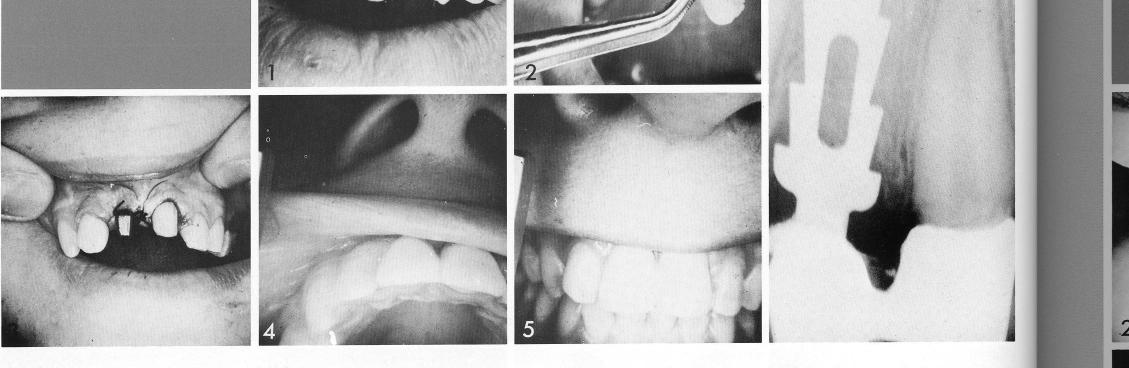

Large diastemas and esthetics (1) suggested a two-unit restoration for the incisors. The abnormal, loose right incisor was extracted (2), and a single-tooth bladevent inserted deep beyond the shallow socket (3). The restoration is a simple, attractive solution (4,5).

1 Two unit maxillary restoration for patient with diastemas and esthetics

2 Maxillary tooth bladevent implant inserted deep beyond shallow socket